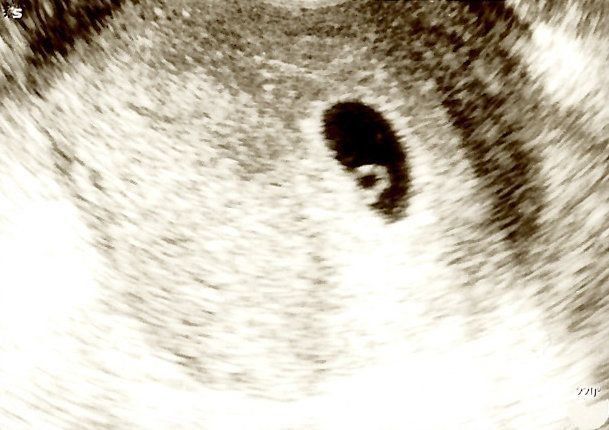

エコー(超音波)画像では液体は黒く、固体は白くうつります。水(のちの羊水)が入っている胎嚢は、黒い円やだ円形のように見えるでしょう。

エコー(超音波)画像で、胎嚢は白く縁どられているように見えます。その中に、卵黄嚢(らんおうのう)と呼ばれる胎盤ができるまでの赤ちゃんの栄養源が白いリングのように見えることもあります。

(超音波写真提供/新村朋美先生)

▲胎嚢の中に、白いリングのように見えるのが卵黄嚢。下のほうに宝石のように赤ちゃんが映っているのがわかります。まるで指輪のようです。

胎嚢の大きさは1.5~2cm程度。早ければ5週末から6週前半には「胎芽(たいが)」と呼ばれる小さな赤ちゃんが確認でき、ほぼ同時に赤ちゃんの心拍も確認できるようになります。

拍動の様子は、エコー(超音波)画像では点滅して見えます。その様子は、白いリングのように見える卵黄嚢にぴかぴか光る石がついたようです。赤ちゃんは徐々に米粒(4~9mm)ほどの大きさになっていきます。